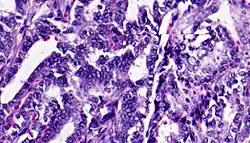

Adenocarcinoma colon | Micrograph of carcinoma colon showing malignant glands.Nuclei are small and vesicular, located at the bottom of the cell. The cells show increased nucleocytoplasmic ratio. | Category: Histopathology of colorectal adenocarcinoma | Colorectal carcinoma |

![]() |